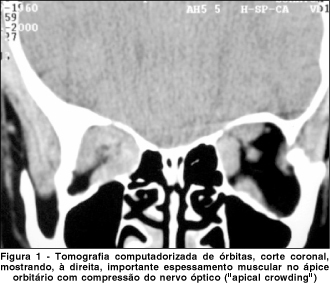

RSP, 33a, feminina, portadora de doença de Graves com orbitopatia há 1 ano. Fazia uso de propiltiuracil (100 mg/dia) e estava descontinuando um esquema de corticoterapia sistêmica (usava prednisona 20 mg/dia). No momento do exame oftalmológico estava com os hormônios tireoidianos normalizados. Referia perda visual progressiva em ambos os olhos há 9 meses e há 20 dias perda total da visão em OD. O exame oftalmológico mostrava retração palpebral superior em ambos os olhos e moderada proptose (exoftalmometria de Hertel 28 mm em OD e 26 mm em OE). O segmento anterior, fundoscopia e pressão intra-ocular eram normais. O exame dos reflexos pupilares revelava defeito pupilar aferente em OD (sinal de Marcus Gunn). A acuidade visual do olho esquerdo era igual a 0,5. No olho direito não havia percepção luminosa. A tomografia computadorizada de órbitas revelou importante espessamento muscular bilateral, com compressão do nervo óptico no ápice orbitário ("apical crowding") à direita (Figura 1). Devido à gravidade do quadro do olho direito, foi imediatamente indicado tratamento cirúrgico descompressivo. Outros testes psicofísicos como campimetria computadorizada e visão de cores, não foram realizados no olho esquerdo antes da cirurgia.

O resultado cirúrgico mais valorizado é o aumento das dimensões do ápice orbitário. Levando-se em conta que o principal mecanismo aventado para a perda visual na OG é a compressão do nervo óptico no ápice orbitário pela musculatura alargada ("apical crowding")(22), é fácil aceitar a noção de que a descompressão orbitária pode realmente beneficiar os pacientes com neuropatia óptica por doença de Graves.